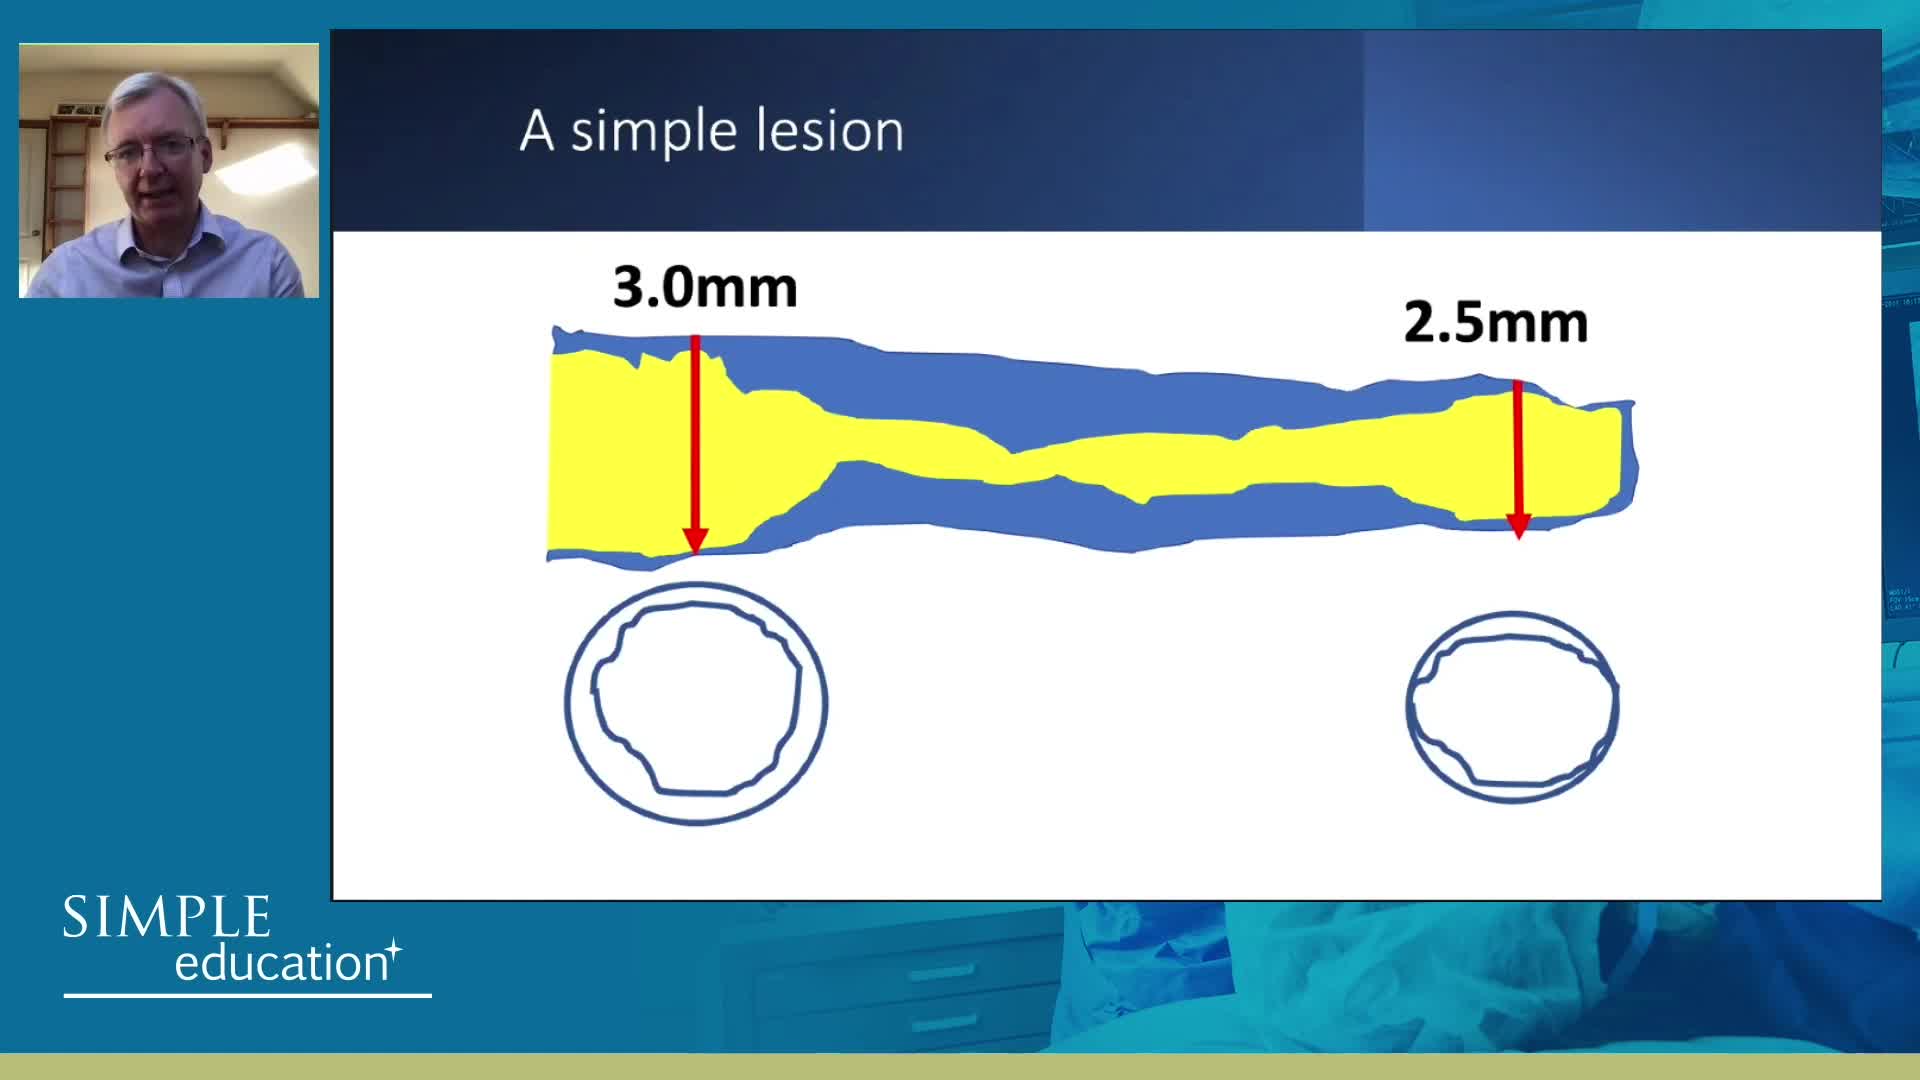

Using SyncVision Co-registration to distinguish between focal and diffuse coronary disease. - Prof Giuseppe Tarantini

Essential steps for physiology-based PCI planning and guidance - Dr Allen Jeremias

Coronary Bifurcations: An Update on Diagnosis, PCI planning and Imaging and PhysiologyGuidance - Dr Dejan Milasinovic